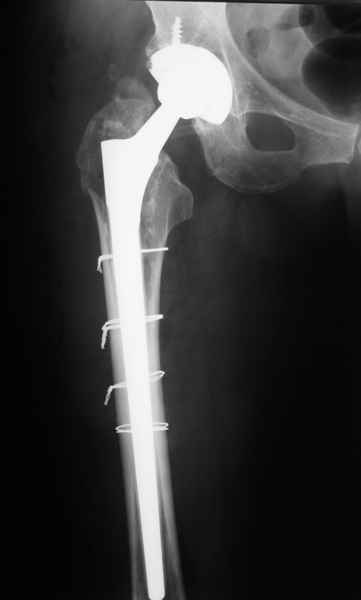

Пациента удалось осмотреть недавно. Достигнутый результат сохраняется. Перелом бедра сросся. Конечность опорная и безболезненная, ходит без трости. Ножка, похоже, реинтегрировалась, как и надеялись. Снимки и фото в приложении. Комментарии приветствуются.

Надо ли что-то делать дальше, как полагаете? Убрать винты? Убрать "удлинитель ножки"? Или оставить все, как есть? Спасибо заранее.